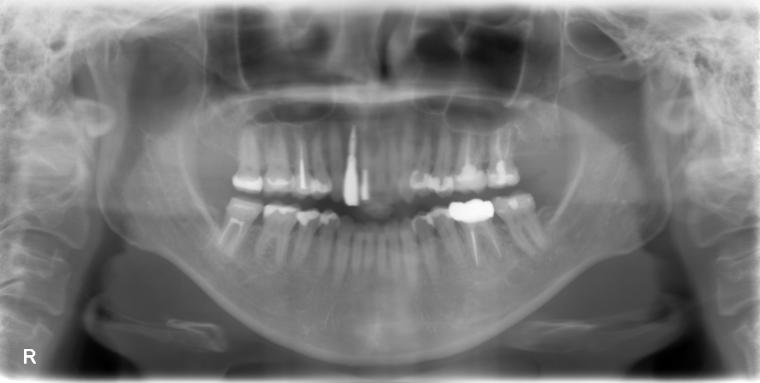

AFTER

53歳女性/上1本欠損/インプラント埋込手術

抜歯後に土台となる骨を作る処置の後、インプラントを1本埋入しました。

現在も定期健診で拝見しております。